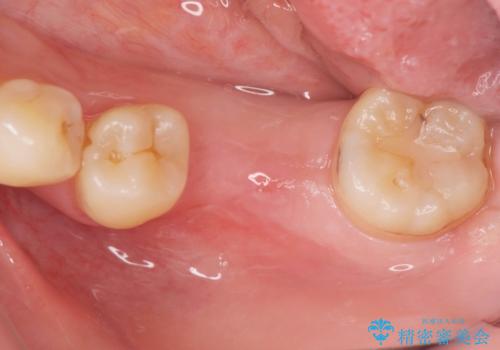

- 左下大臼歯が噛みしめにより割れてしまい、抜去後のインプラント治療を希望され来院されました。

しっかりと咬合負担能力の増えるインプラントによる欠損補綴を計画します。